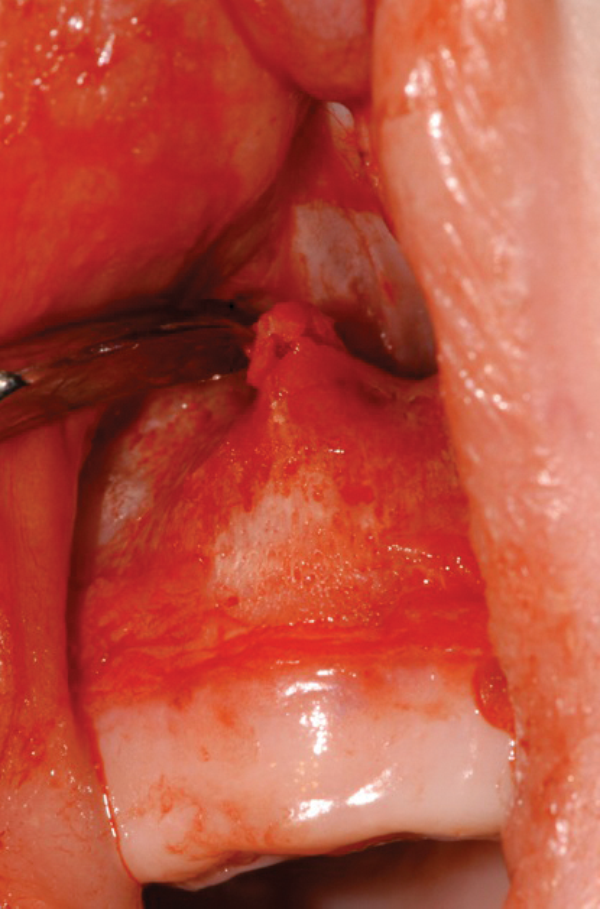

Figure 2: The stenosed pyriform aperture is approached through a sublabial incision.

- The stenosed pyriform aperture is approached through a sublabial incision (Figure 2).